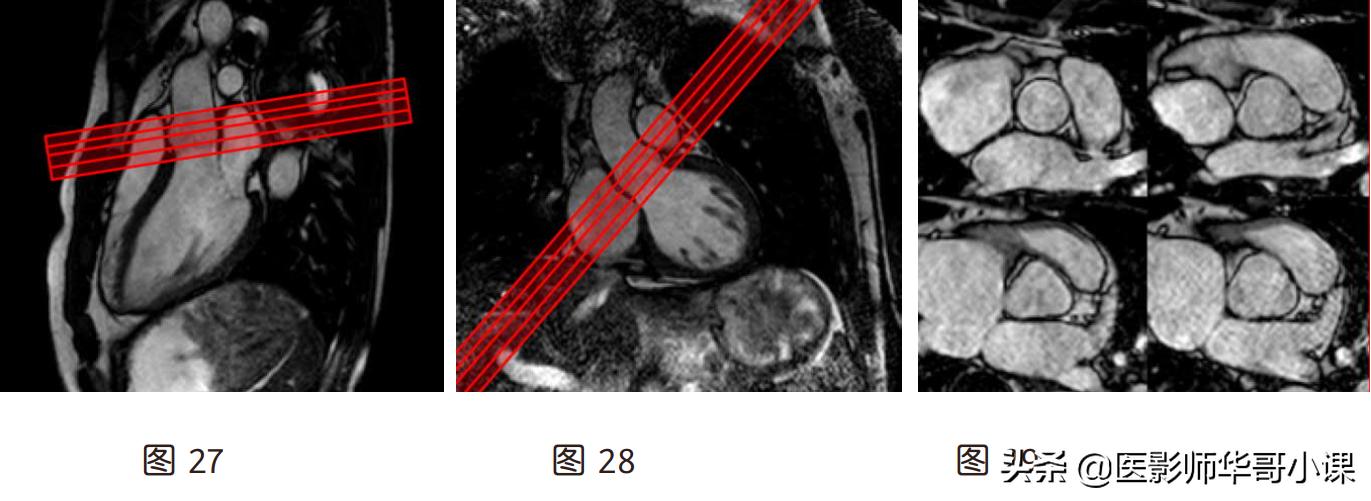

3.形态学扫描方法:

- 黑血常用 TSE 的 T1、T2、STIR 序列扫描两腔、四腔、短轴位各扫描一遍(短轴序列为

- 多层,应当从心尖向心底方向逐层扫描,每一层屏气一次,过程比较繁琐。要简化扫描流程

- 时,至少在心尖、室间隔中部、心底各扫描一层)

- 亮血序列扫描位置方法与黑血一样